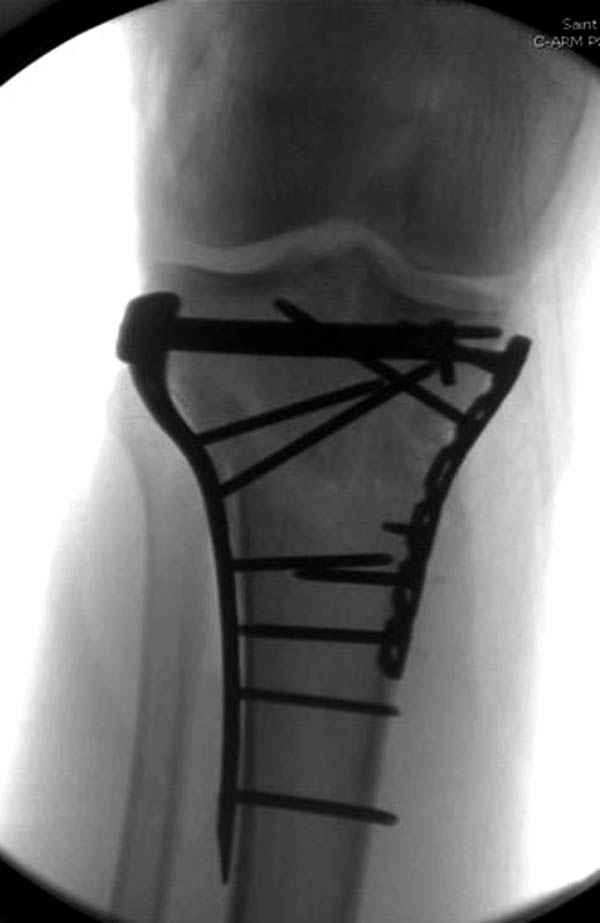

Уважаемые коллеги! В прошлую пятницу больной прооперирован - как и планировалось мыщелковая LCP от ChM. Малоинвазивно не получилось - один большой доступ :(. (но с минимальным скелетированием б/б кости). Наружный мыщелок собрали, но по контролю видно, что задне-медиальный отдел метаэпифиза смещен. Фиксировать не стали (?). 4-е сутки после операции - по м/тканям без проблем. Дополнительная иммобилизация синтетическим тутором.

P. S. перелом диафиза на контроле не совсем захвачен, но проблем там нет. Приношу извинения за низкое качество Р-грамм - выполнены на сканере (фотоаппарат не работает :)) .

Трудно поверить, что разрекламированная Ортопедическая школа Восточной Украины позволяет такие странные снимки? На прямом снимке сохранен общий контур плато, но не известна судьба импрессии суставной поверхности. На полубоковой?, оставлен без репозиции задне-медиальный отдел, и навряд ли после такой фиксации можно удовлетвориться результатом.

Такая ситуация характерна для многих, когда принимается ошибочное решение, т.е пытаются фиксировать одним имплантом переломы двух мыщелков. Латеральная пластина приемлема только для тех случаев, когда сохраняется интактным медиальный диафизарный кортекс и отсутствует фрагментация на верхушке медиального перелома.

Представленные снимки не информативны, нужны отдельные качественные снимки коленного сустава и голени без ротации.